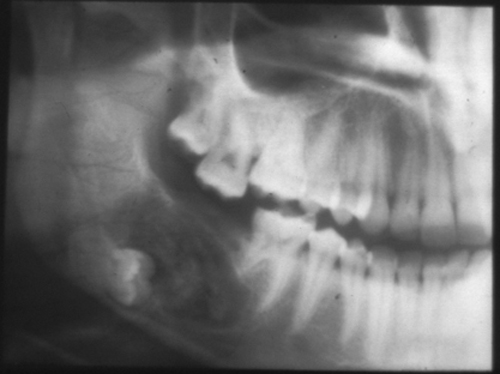

Одонтома нижней челюсти: фотографии и медицинская информация

Раздел: Фотобанк решений